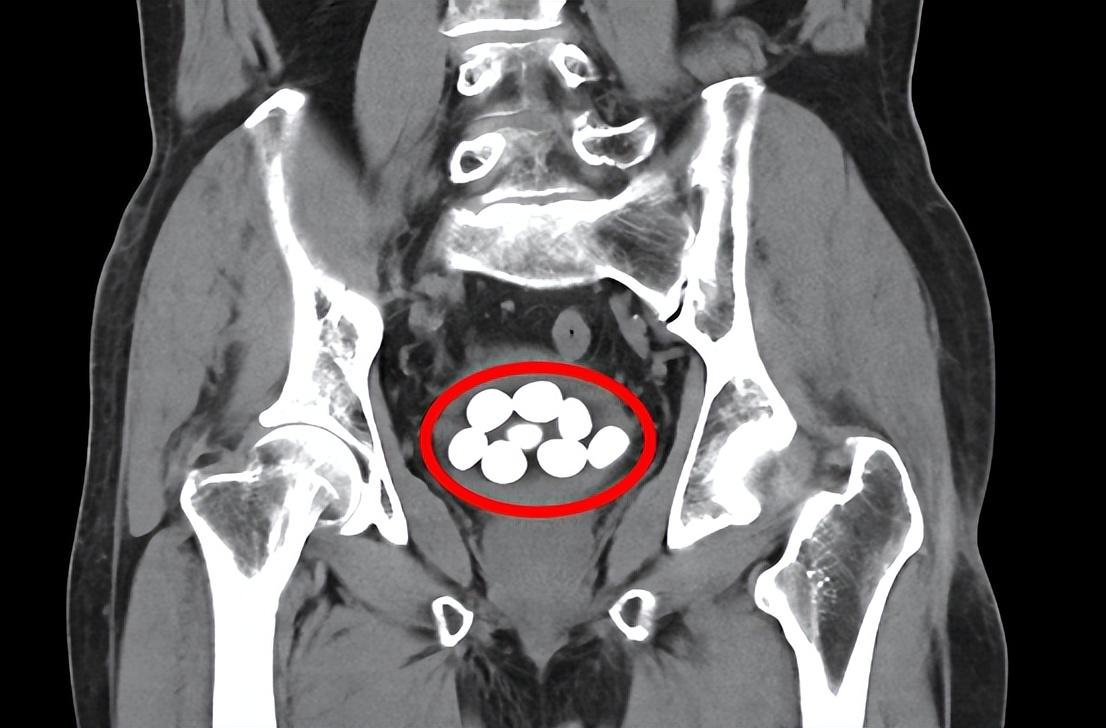

85岁老人9颗膀胱结石分别击碎取出

平南县第二人民医院泌尿外科为一位85岁老人成功实施经尿道膀胱结石碎石术和前列腺电切手术,将9颗膀胱结石分别击碎取出,解除了老人的病痛之苦。整个手术持续近2个多小时,术后第四天,经泌尿外科专科护理团队的精心护理,患者顺利出院。